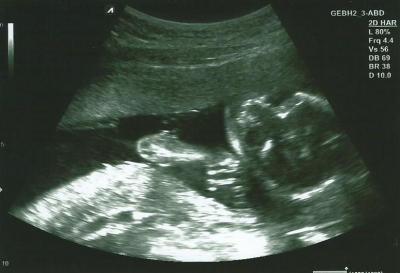

Also es bleibt bei einem Mädchen :) Sie ist kerngesund und hat gezappelt ohne Ende! Der Papa hat es heute überraschender Weise zum Termin geschafft, ich dachte er wäre wieder nicht dabei! Umso schöner Mein ET wurde auf den 31.10 korrigiert, es bleibt aber komischer Weise bei 18+5. Meine alte FÄ hat sich wohl verrechnet Nach der große des Kindes würde sie mich sogar noch weiter vordatieren auf 19+1 aber sie sagte wir behalten jetzt den 31.10. Finde ich auch okay Hab eine Überweisung zum Doppler und Feindiagnostik bekommen, muss mir nur noch einen Termin machen! Und ein ganz hübsches Bild hab ich bekommen

Bild zu FA Bericht - Forum für November - Mamis

Das freut mich das alles gut ist. Immer nieder schön zu hören wenn alle gesund sind. Aber das Bild kann ich leider nicht erkennen was was ist?

Freut mich auch, dass alles gut ist! Rechts ist meiner Meinung der Kopf!?

Glückwunsch zum Mädchen kann leider auch nix erkennen sieht so aus wie der Kopf oder

Meinem Mann musste ich das auch erklären ;) Also der Kopf ist rechts, man sieht das Gesicht eigentlich recht gut. Und unten ist der Arm, die Hand hält die Kleine am Kopf. Ich erkenne es wahrscheinlich auch nur, weil ich beim Ultraschall dabei war ^^